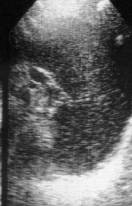

Clinical case. 52-year-old patient with multiple myeloma complicated

with chronic renal failure.

Fig. 3. Ultrasound diagnostic. Hypersplenism. Heterogeniety echo.